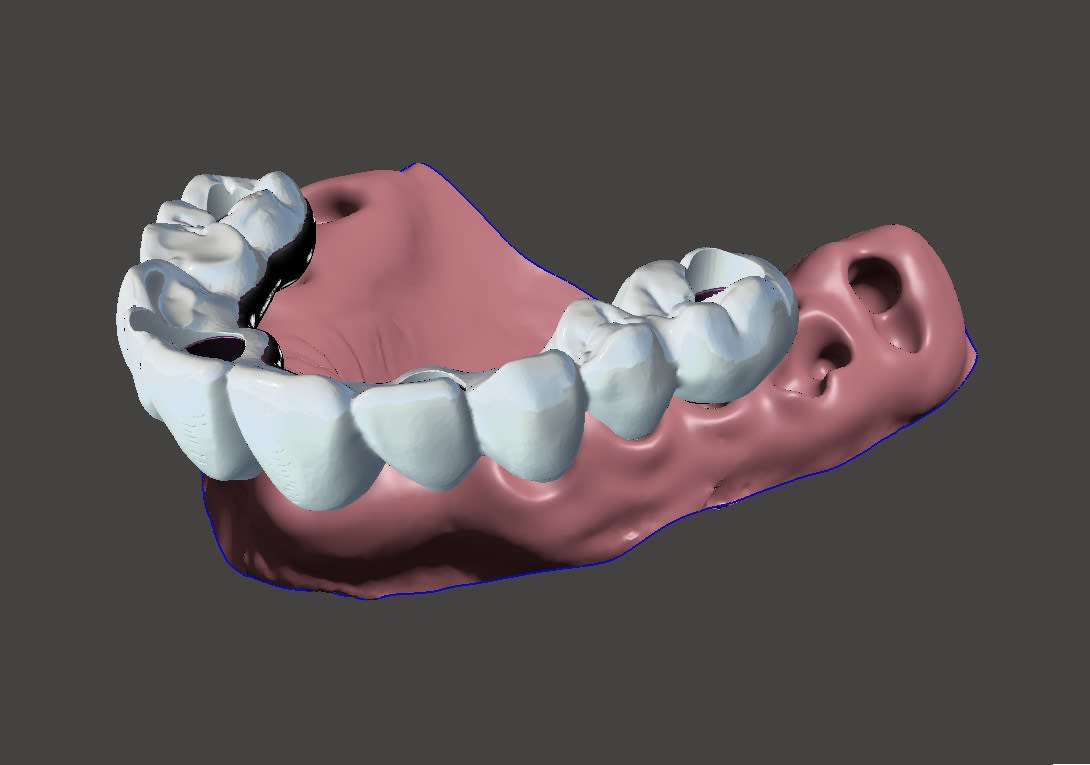

Autre cas en septembre. Toujours un guide à étage prevu. Cette fois avec lambeau pour expansion et sticky bone. Le sujet du post est " quel guide, pourquoi faire ". En fait, selon le cas, je vais choisir un guide osseux, avec ou sans étage, un prov avec ou sans armature metal, suivant la porté entre les implants, le support osseux accessible ou non...C'est assez au feeling, pendant la planif que je décide du type de guide .

Je n'ai pas encore complétement confiance a la résine imprimé pour un all on 4, sans fausse gencive: beaucoup de portée entre les implants, et une épaisseur de résine limité, même si je sais que certain le font.

Ici : étage clavette positionné avec support dentaire, guide de forage full guided , trousse ETK, positionnement du bridge prov sur l’étage clavette , bridge avec armature métal et pilier collés en bouche.